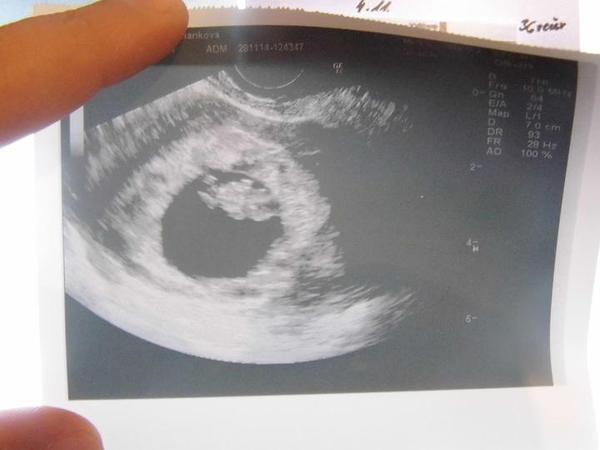

Ahoj holky, tak dnes se se mnou rozloučili v Caru a v pondělí jdu na kontrolu již k Dr. Vše v pohodě, prcek má necelý 1,5cm, ale hematom se zvětšil, takže fakt nohy hore a odpočívat. Tady máte zase ukázku toho šmudly našeho 😀